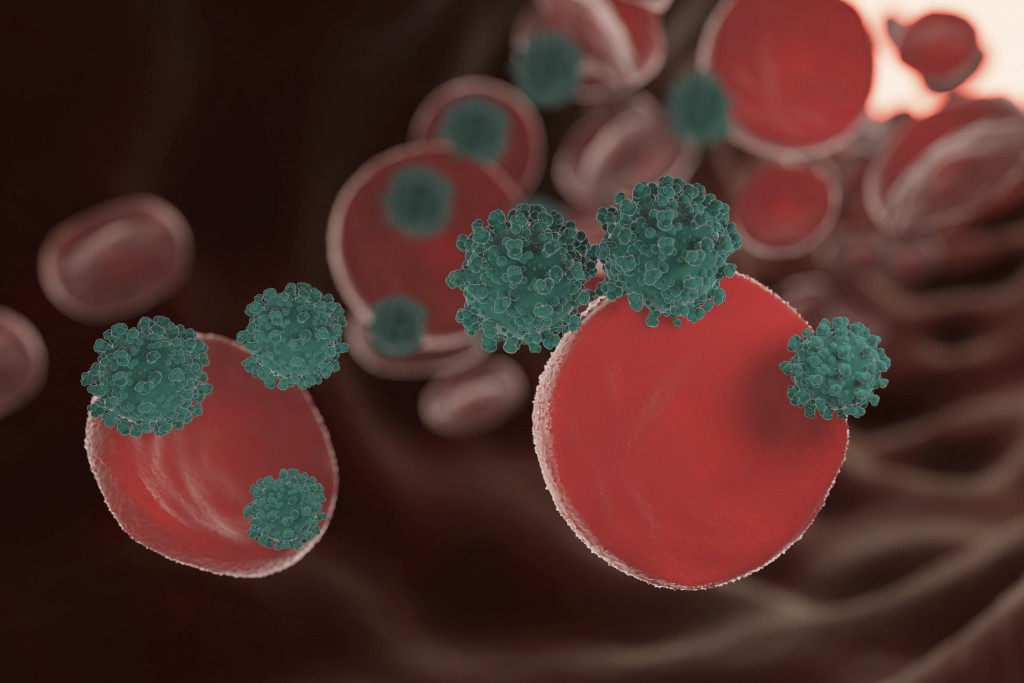

Лейкоз, который часто называют раком крови либо лейкемией, относится к тяжёлым онкологическим заболеваниям. Он поражает кроветворные органы и вызывает изменения, из-за которых в крови больного резко увеличивается количество лейкоцитов. С развитием заболевания кровь постепенно перестаёт выполнять свои функции в организме, из-за чего при отсутствии лечения наступает летальный исход. Болезнь поражает не только взрослых, но и детей, с одинаковой частотой обнаруживается у мужчин и женщин.

- острые, характеризующиеся быстрым развитием и образованием большого количества незрелых клеток крови — бластов;

- хронические, которым свойственно длительное течение и патологическое продуцирование зрелых лейкоцитов с изменёнными свойствами.

Кроме того, онкологи выделяют множество видов лейкозов по типам клеток, патологическое изменение которых лежит в основе заболевания. По этому принципу различают лимфобластные, монобластные, миелобластные, лимфоцитарные, миеломные и другие разновидности болезни.